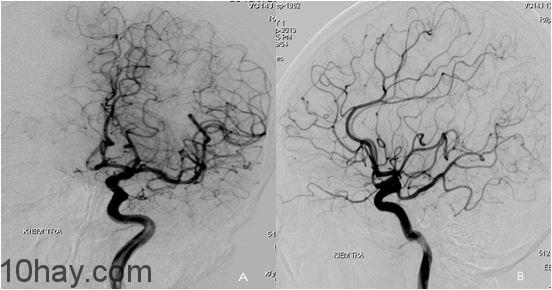

7. X Quang kỹ thuật số xóa nền (DSA)

X Quang kỹ thuật số xóa nền (Digital Subtraction Angiography – DSA) là một hệ thống chụp hình mạch máu mới bằng tia X. Đây là sản phẩm của sự kết hợp giữa kỹ thuật chụp hình mạch máu thông thường theo kỹ thuật Seldinger với kỹ thuật xử lý hình ảnh bằng máy vi tính.

Một hệ thống DSA thường bao gồm các thành phần như bộ phận phát tia X, bộ phận thu nhận hình ảnh, bộ phận xử lý hình ảnh số và bộ phận hiển thị….Bộ phận trung tâm của hệ thống là bộ xử lý hình ảnh số (digital image processing system).

Như vậy nguyên lý cơ bản của hệ thống chụp DSA là dùng ánh sáng huỳnh quang và tia X chụp hình mạch máu ở những vị trí cần kiểm tra khi chưa bơm thuốc cản quang và sau khi đã bơm thuốc cản quang vào mạch máu cần chụp. Máy tính sẽ xóa mờ hình ảnh nền để làm rõ hệ thống mạch máu.

Trước khi chụp DSA, bệnh nhân phải được chuẩn bị kỹ: xét nghiệm máu, chụp X-quang phổi, ghi điện tâm đồ và nhịn ăn sáng. Bệnh nhân được đưa một ống thông vào lòng mạch máu từ bẹn lên đến động mạch cần chụp để bơm thuốc cản quang.